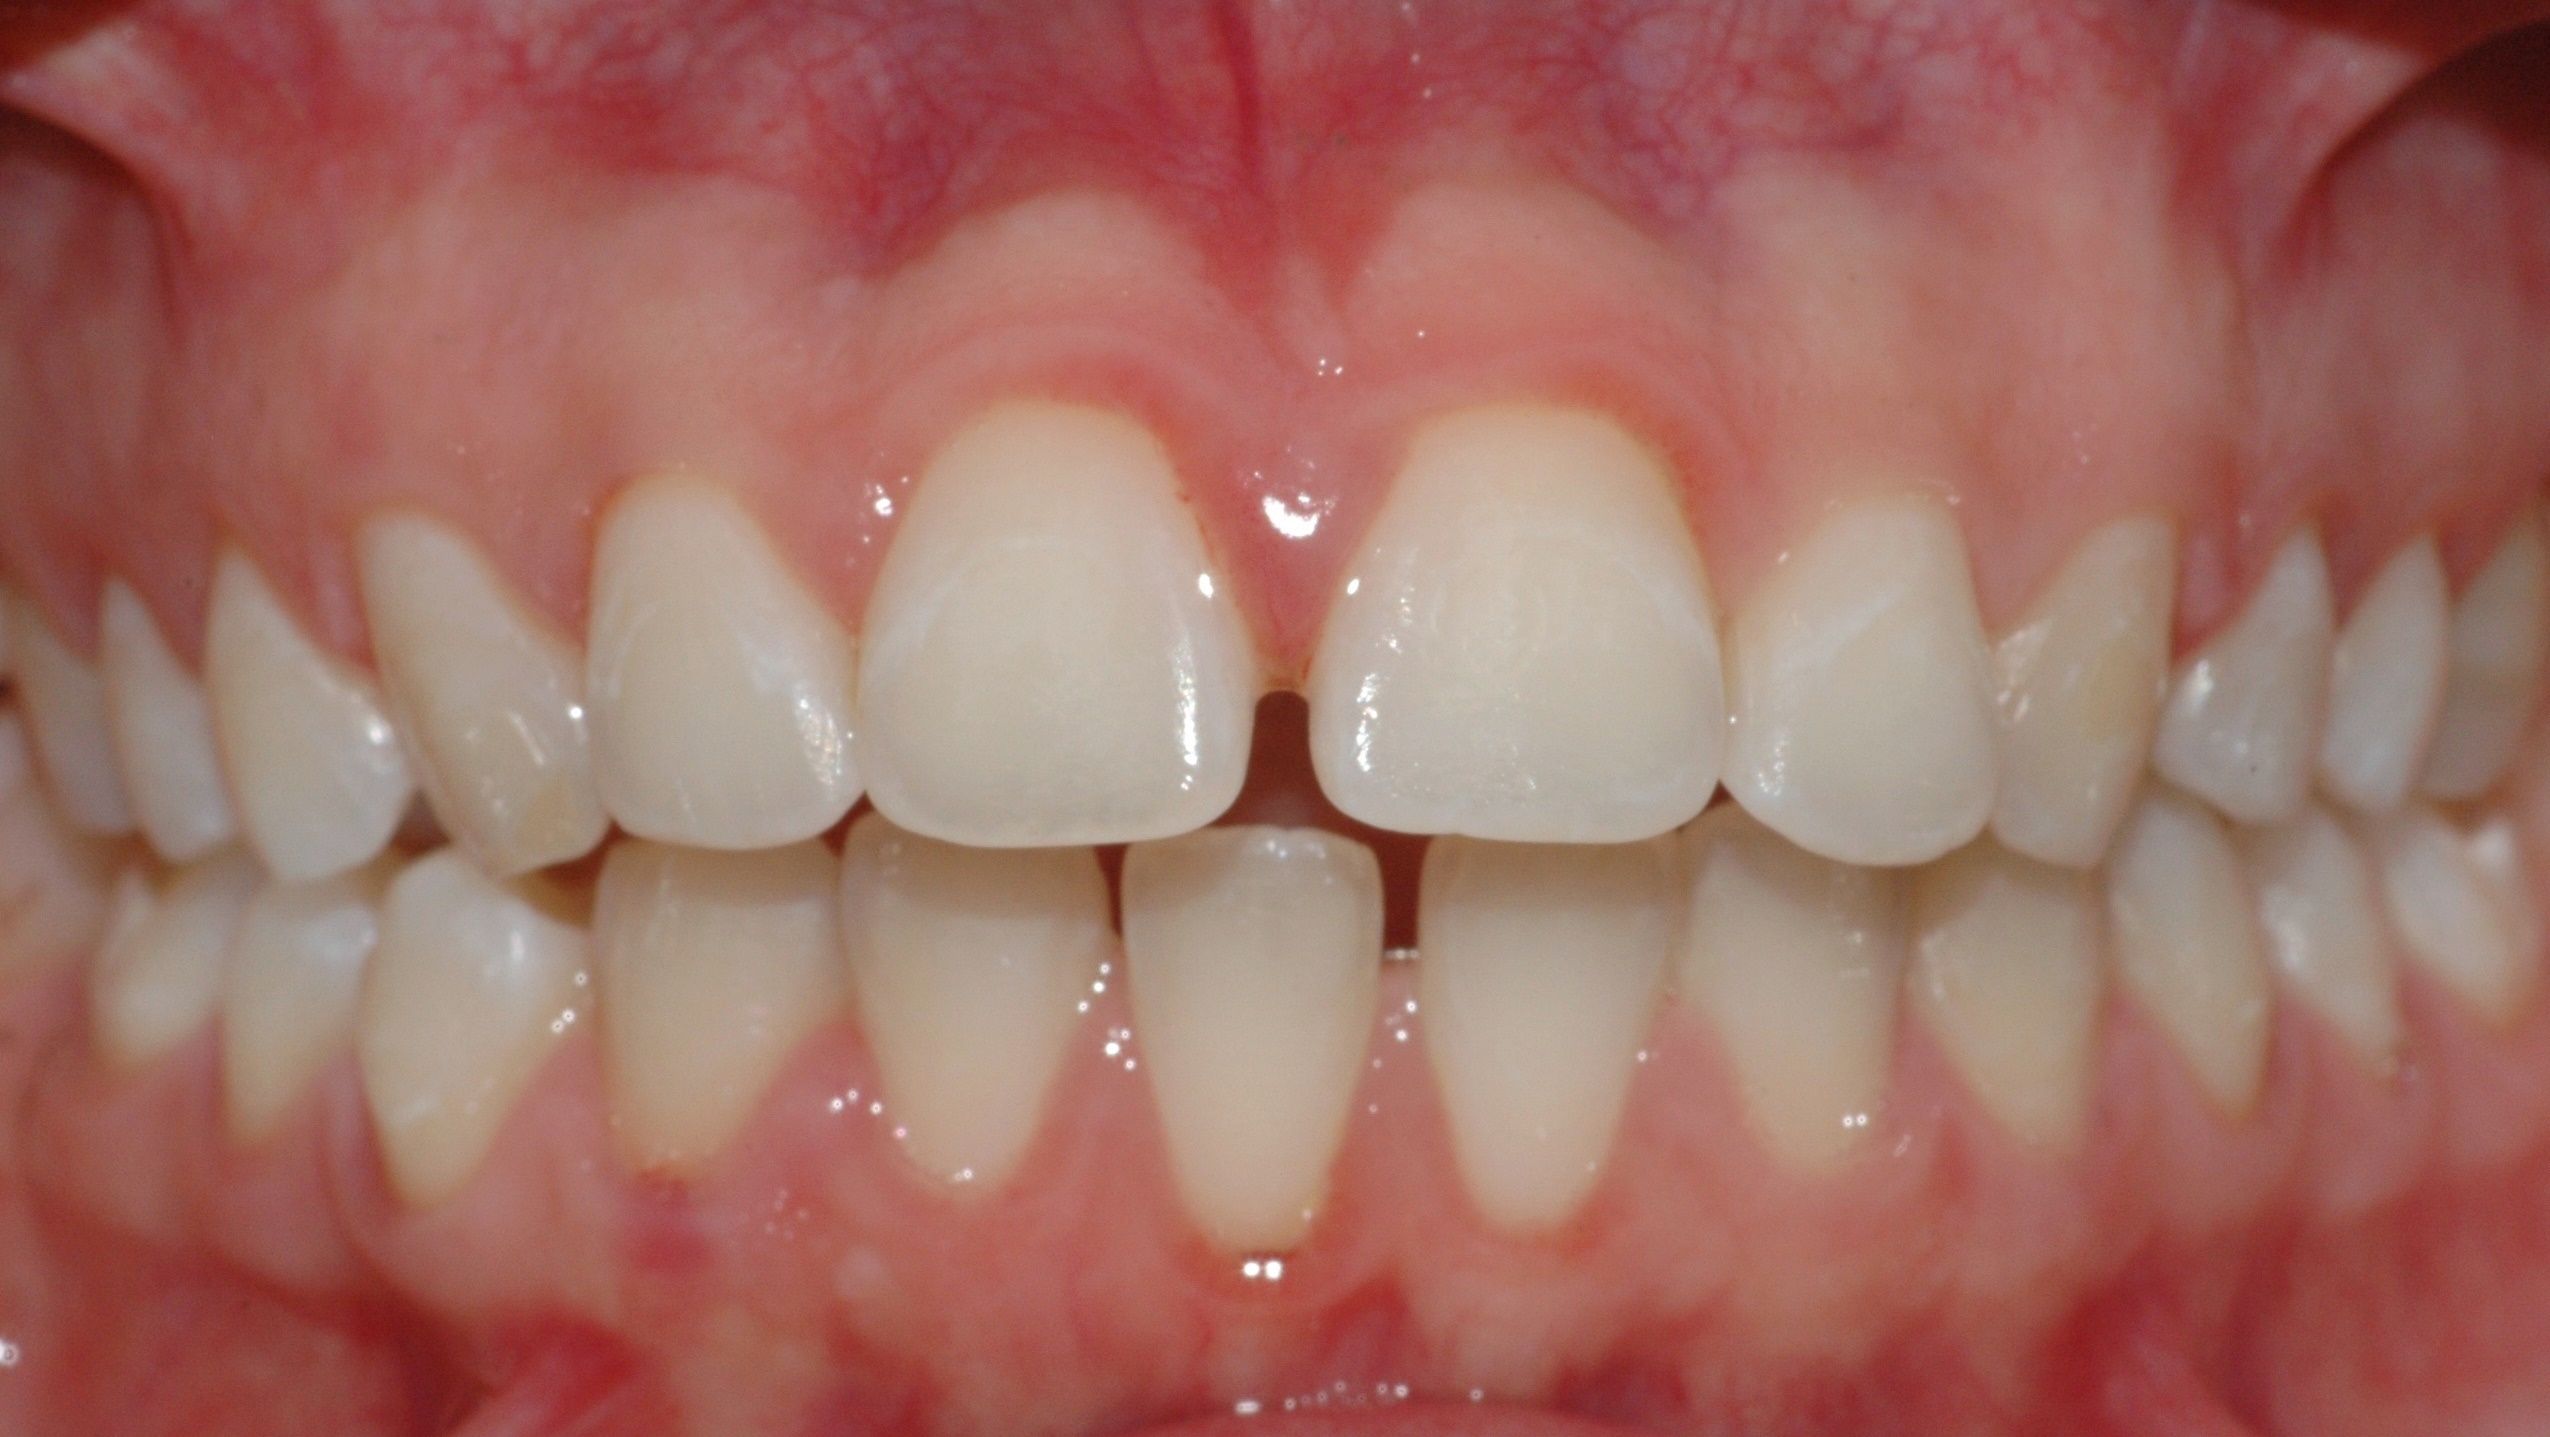

Caso clinico

La paziente si presenta a causa del malposizionamento del canino superiore di sinistra, ruotato lungo il suo asse di quasi 90 gradi. In seguito ad un trattamento con allineatori trasparenti di circa 7 mesi, il dente è stato portato in posizione assolutamente idonea.

La paziente si presenta con la richiesta di chiudere il diastema presente tra gli incisivi superiori, sia per motivi estetici, sia a causa di una forte infiammazione gengivale provocata dall’intasamento alimentare (food impaction) nello spazio aperto. In 6 mesi di tempo, il trattamento tramite allineatori, ha chiuso lo spazio e risolto il problema a livello gengivale.

PRIMA

DOPO